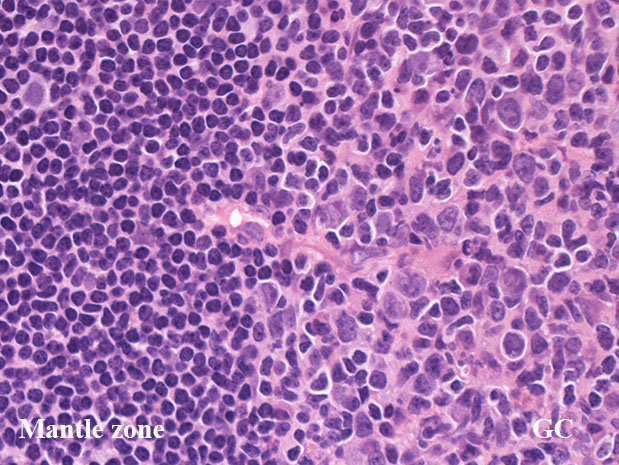

GC01.jpg

リンパ節の皮質cortexは, primary follicle(一次濾胞)とsecondary follicle(二次濾胞; 右図)から構成される.

primary follicle;

主にナイーブB細胞と記憶B細胞から構成され, μおよびδ重鎖とポリクローン性の軽鎖を細胞に表出させている. 形態的には小型リンパ球からなり胚中心はなく, small/ large cleaved cellは見られない.

bcl-2陽性. CD10, bcl-6は陰性. bcl-2陽性の一次濾胞をFLと間違えないよう注意.

secondary follicle;

胚中心(germinal center: GC)とmantle zoneをもつ.

mantle zoneはprimary follicle構成細胞と同じB細胞からなる. mantle zoneには厚い薄いがみられ, 薄いときはmantle zoneがないように見え, 子供のリンパ節に多い.

germinal center(GC)は, B細胞, T細胞, 抗原提示細胞, tindible-body macrophageが混在して構成されている. B細胞が優位に多く, small/ large cleaved cell(centrocytes)とlarge non-cleaved cells(centroblasts)が認められる。

正常胚中心のcentrocyte, centroblastsはbcl-2陰性であり, CD10, bcl-6が陽性となる. surface Igは低レベルであるが細胞質に通常 μ重鎖タイプ(IgM)Igが認められる.

T細胞はCD4+/ CD8-のhelper/inducer cellsであり, follicular (helper)T-cell:Tfhとよばれる. PD-1+, CXCL13+, CD57+.

抗原提示細胞の多くは follicular dendritic cellであり, 提示抗原からmyofibroblastの特殊型細胞で骨髄のstromal cell前駆細胞由来と考えられている.通常この細胞は組織学的に区別しがたいが, 微細な傾向のクロマチン, 明瞭な小型核小体をもち細胞質が不明瞭な2核/多核細胞(Warthin-Finkeldey cell)があればfollicular dendritic cellとして区別できる.

CD21+, CD35+, CD23+とclusterin+ CD23はときに陰性のことがあるので注意.

高度に活性化された胚中心では, centrocyteとT細胞から構成される light zone (LZ)と増殖の盛んなcentroblastsとtindible-body macrophageの多いdark zone(DZ)が区分されるようになり, 極性(polarization)をもつといわれる.

ときにmantle zoneの外側にmarginal zoneが認められることがあり, 腸管膜リンパ節によく見られる.